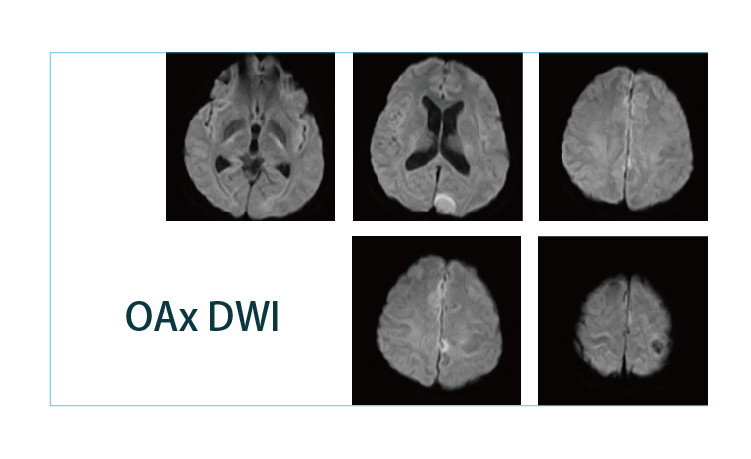

【朗润影像档案】20190419磁共振影像病例结果讨论

【朗润影像档案】磁共振影像病例分享(编号20190419)